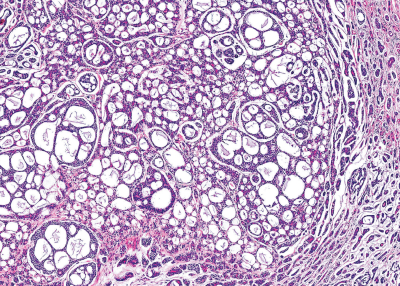

75歳の女性。左側口底の腫瘤を主訴として来院した。5か月前に気付いたが、疼痛がないためそのままにしていたという。初診時の口腔内写真、CT、MRI T2 強調像及び生検時の H-E 染色病理組織像を別に示す。